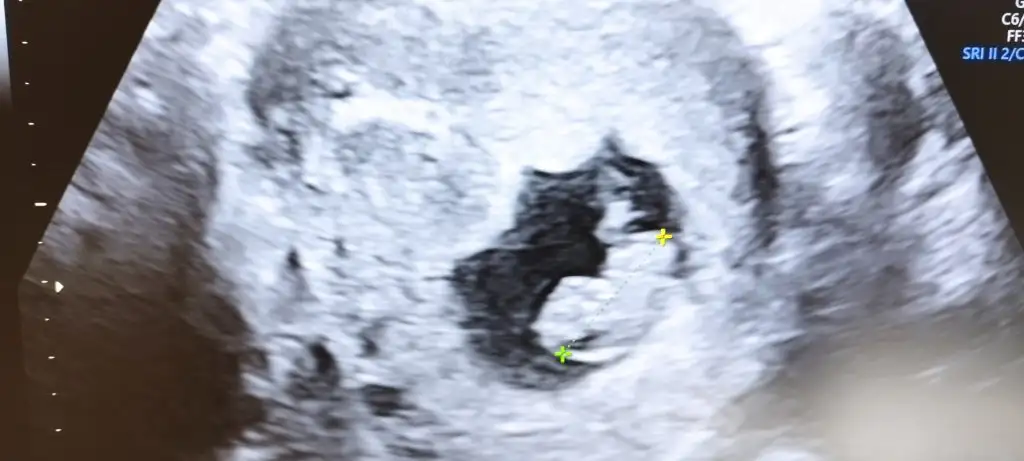

Merhaba bebeğim 10 haftalık. Benim içinde yorum yapar mısınız. teşekkürler <3Selam Kızlarbir çok kişi gruplardan beni bilir. Yine yetiştim imdatlara

5 ve 14. haftaya kadar olan ultrason fotolarınızı paylaşın. Vajinadan mı yoksa karından mı çekildiğini ve kaç haftalık olduğunu da mutlaka belirtin.